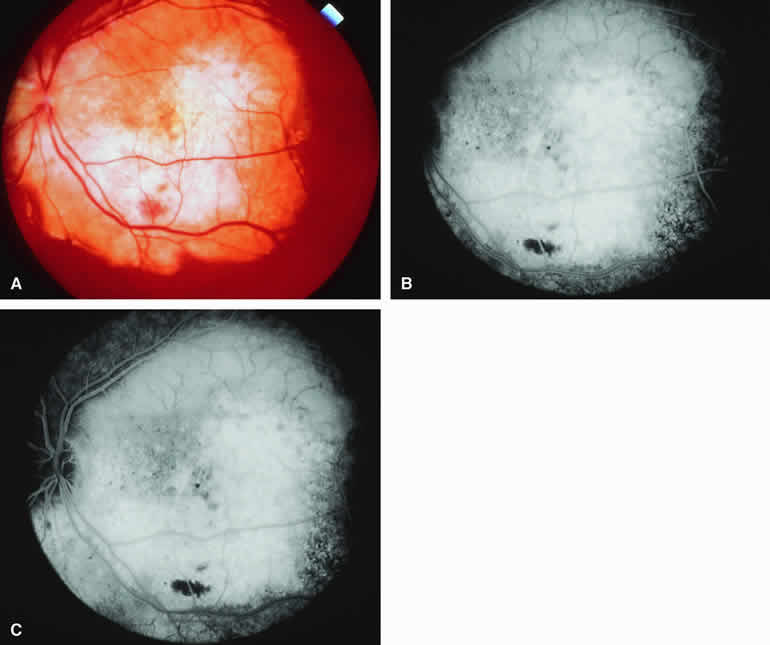

Amelanotic Choroidal Nevus

Approximately 10% to 15% of choroidal nevi are largely or completely amelanotic clinically. Fluorescein and ICG angiography of an amelanotic choroidal nevus (see Fig. 3) tend to show less prominent hypofluorescence of the lesion than they do with darkly melanotic nevi. Because of the lack of intracellular melanin pigment within the nevus cells, some large-caliber choroidal blood vessels running through the nevus may be visible in the region of the mass (see Fig. 3B and C). These choroidal blood vessels are better defined by ICG angiography than by fluorescein angiography. Amelanotic choroidal nevi often appear mildly hyperfluorescent in late-phase frames (see Fig. 3D).